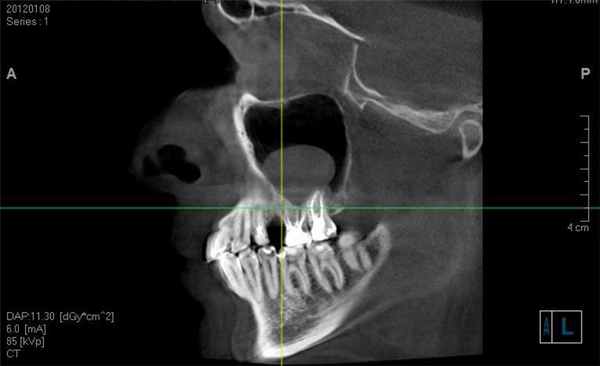

- ортопантограмма ( панорамная рентгенограмма челюсти)

- КТ околоносовых пазух

Для выбора адекватного хирургического доступа большое значение имеет СКТ ОНП, позволяющая определить локализацию кисты, при этом важную роль играет сагиттальная реконструкция, дающая возможность оценить взаимоотношения кисты с передней и задней стенками пазух [26, 34, 35].

В 70% случаев кисты ВЧП локализуются на задне-верхней стенке, в латеральных отделах верхней стенки и в области естественного соустья пазухи, что позволяет удалить их эндоназальным доступом через средний носовой ход [26]. В случаях локализации кисты на передней и медиальной стенках ВЧП, а также в альвеолярной бухте эндоназальный подход через средний носовой ход зачастую не позволяет полностью удалить кисту и, следовательно, требуются другие варианты либо комбинированный доступ.